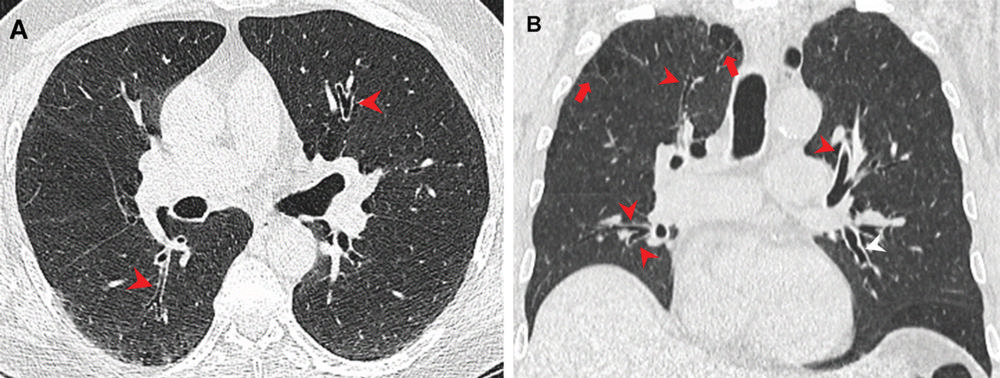

Figure 2. Airway changes in a 66-year-old male marijuana and tobacco smoker with cylindrical bronchiectasis and bronchial wall thickening (arrowheads) in multiple lung lobes in a background of paraseptal and centrilobular emphysema. (Courtesy of Radiology)